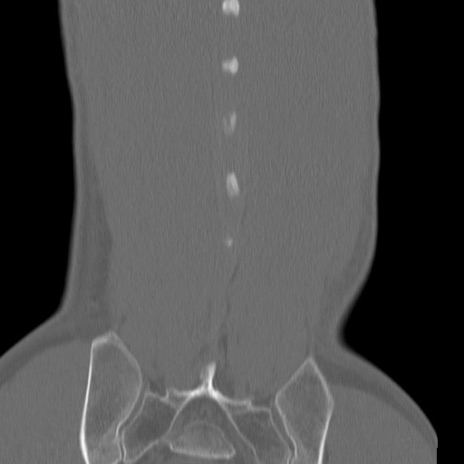

症例3 腰椎CT(冠状断像)

【症例】30歳代男性

【主訴】腰痛

【現病歴】本日旅行先で観光中に、友人と衝突し転倒し受傷。

【身体所見】麻痺なし、右下腿内側前面外側、左下腿内側に知覚鈍麻・しびれ

異常所見と診断は?

矢状断像